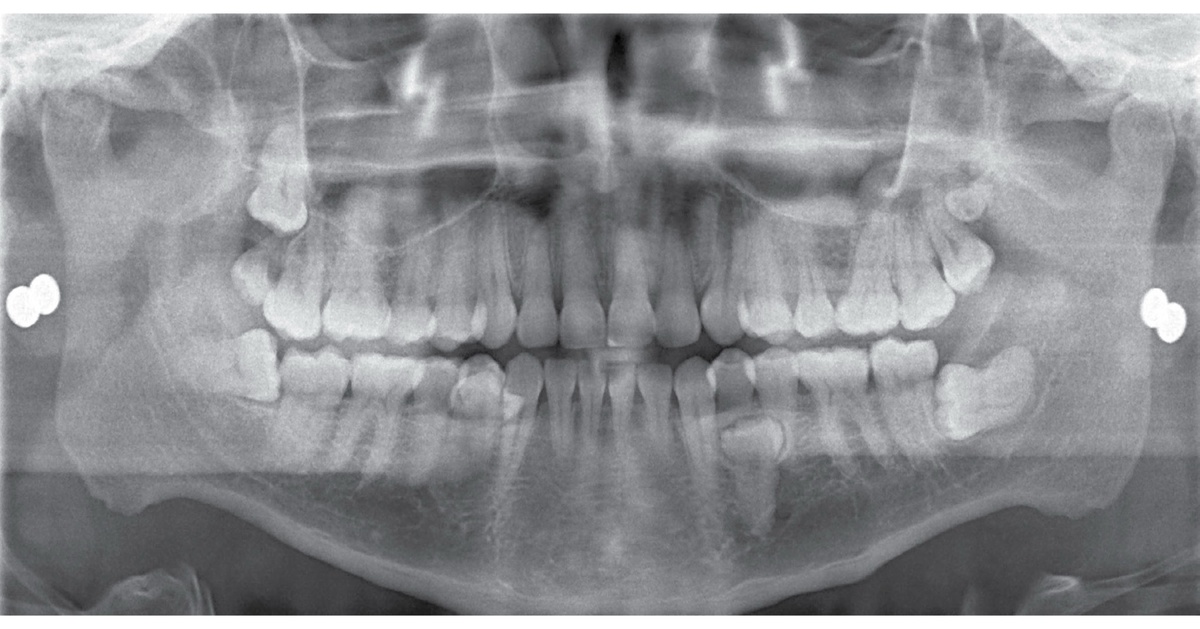

Цифровая ортопантомограмма на аппарате DEXIS OP 3D Pro позволила получить визуализацию всех четырех сверхкомплектных зубов.

Панорамный снимок (OP 3D Pro) демонстрирует целый ряд сверхкомплектных и ретенированных зубов.

Панорамный снимок и ТРГ, полученные на томографе DEXIS OP 3D Pro позволили специалистам, включая хирурга, пародонтолога и стоматолога общей практики, составить полноценный план лечения пациента.

Благодаря технологиям получения и построения 3D-изображений хирург-стоматолог смог точно определить расположение ретенированных третьих моляров нижней челюсти вблизи нижнечелюстного нерва, а также четко оценить местоположение сверхкомплектных зубов вблизи структур ментального нерва.

Изначально пациент обратился с жалобами на сильную боль в правом нижнем квадранте и периодическую боль в левом нижнем квадранте. Мы провели первичные обследования: 2D-панорамный снимок и КЛКТ- исследование на томографе DEXIS OP 3D Pro (область сканирования FOV 8 x ø 15 см) при стандартном разрешении (90 кВп, 8 мА, время экспозиции 4,5 секунды). Мы обнаружили прорезавшийся сверхкомплектный зуб в нижнем квадранте слева.